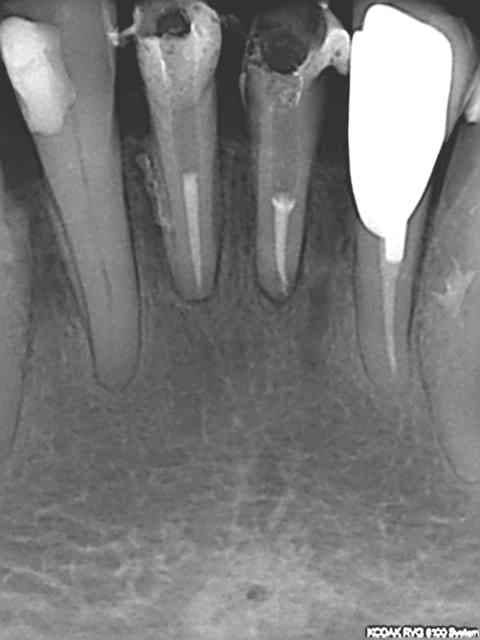

Radio cône en place avant de le sceller, avec un bon tuck- back et le machtou chauffé au rouge il est rare que le cône reste collé au fouloir. L'avantage de faire la provisoire dans la séance permet de descendre la couronne en plateau et de bien visualiser la chambre pulpaire, particulièrement indiqué dans le cas ci dessus sur des 31 41 d'une personne âgée pulpe rétractée ou à force de la chercher tu trouves .... le desmodonte !))))).

Re-belotte. 15.

et un bon vieux mordu, le tout 40 mn productivité !))))